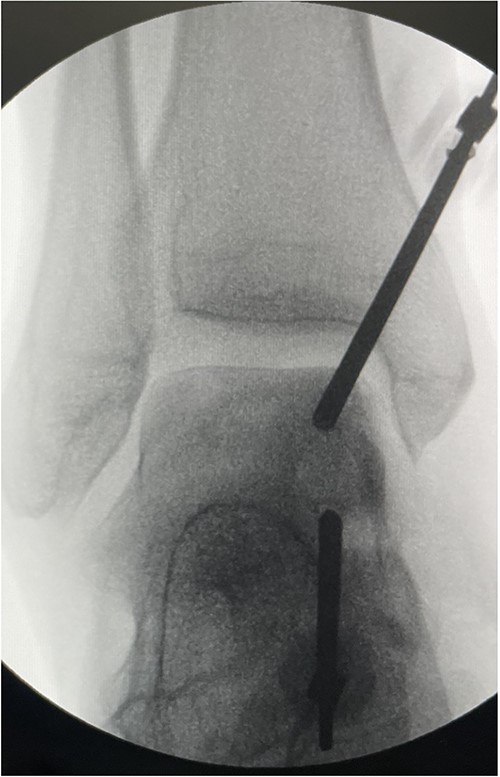

He presented with no relevant medical history and worked as a chemical plant supervisor, which required continuous movement throughout the day. Clinical examination revealed deep-seated pain around the medial aspect of the ankle with an intact range of motion and ankle alignment. His MOXFQ score was 48/80. CT scan revealed a large but well-contained, subchondral cyst in the medial talus of the ankle (Fig. 4).